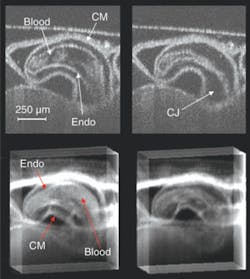

Medical cardiac-gated imaging modalities derive a gating trigger from the electrocardiogram (EKG) of the patient. Unfortunately, the electrical signal from a preseptated embryonic heart is minute and to record it electrodes would have to be placed virtually in contact with the heart, which is invasive from the perspective of the embryo. The precise placement of the electrodes is extremely challenging and it is not clear that adequate signals can be obtained from early embryos. To circumvent this problem we derived a gating signal using laser Doppler velocimetry (LDV) to noninvasively extract a flow signal from one of the outer vitelline vessels. As a demonstration, we recorded a 4-D image set of an in vivo beating quail heart (day two of development) consisting of 864,000 axial scans over multiple heartbeats. The data set represents full 3-D volumes at eight time points through the heart cycle (see Fig. 2).

The OCT sum-voxel projection images (or slices) of the heart in diastole and systole clearly resolve important anatomical features such as the compact myocardium and the endocardium, and demonstrate the image quality achievable with this technique. Sum-voxel projection allows us to easily visualize and interpret a 3-D image, revealing the outer and inner surfaces of the heart and how the heart is positioned within the surrounding tissue. The 3-D structure of the heart becomes further evident by projecting along various angles to visualize the volume while it rotates.